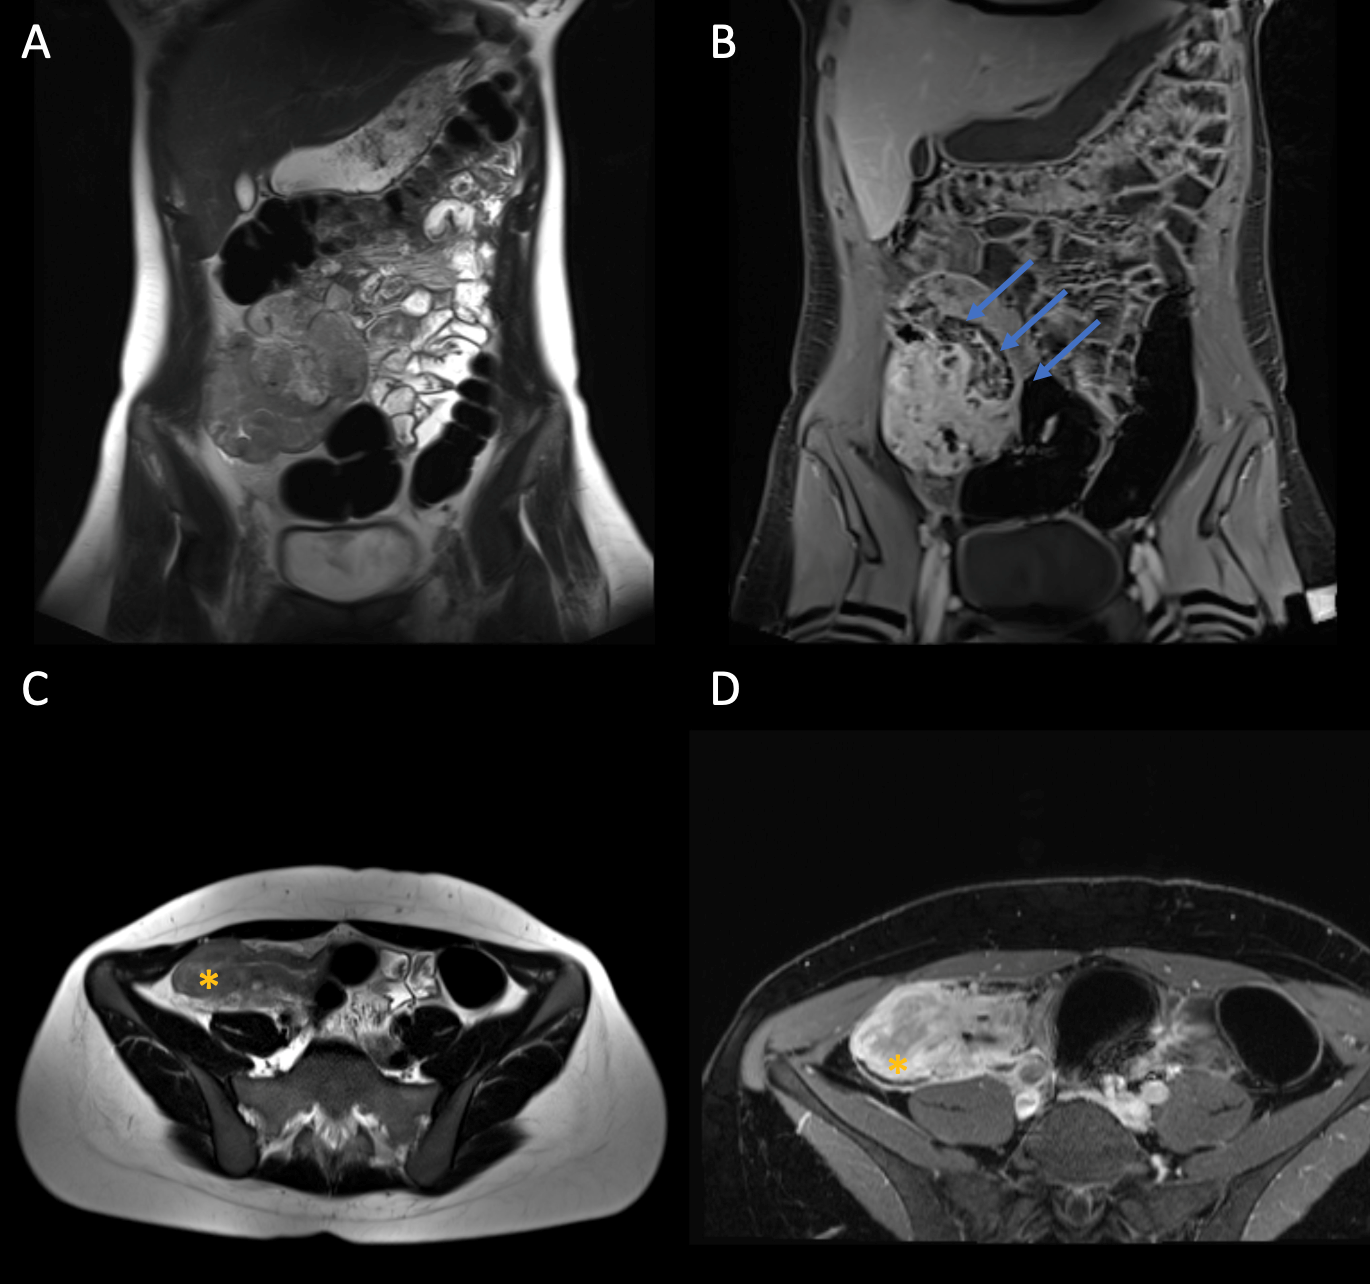

Abbildung (siehe oben) A: T2w HASTE coronal. B: Fettgesättigte T1w Post-KM FS coronal. C: T2w HASTE axial. D: Fettgesättigte T1w Post-KM axial. Blaue Pfeil: Konglomerattumor im rechten Unterbauch. Stern: Ausgeprägte Wandverdickung des terminalen Ileums.

Bei der Patientin wurde eine Ileitis terminalis bei Morbus Crohn festgestellt. Morbus Crohn ist eine chronisch-entzündliche Darmerkrankung (CED), die sich durch eine Entzündung in verschiedenen Bereichen des Verdauungstrakts auszeichnet. Die Entzündung tritt in der Regel in der Darmwand des terminalen Ileums auf, kann jedoch auch in umliegenden Geweben (Lymphknoten und Fettgewebe) auftreten und zu einem Konglomerattumor führen, wie es der Fall bei Frau M. ist. Manchmal kommt es ebenfalls zu einer Fistelbildung zwischen Ileum und Harnblase oder Ileum und Sigma.